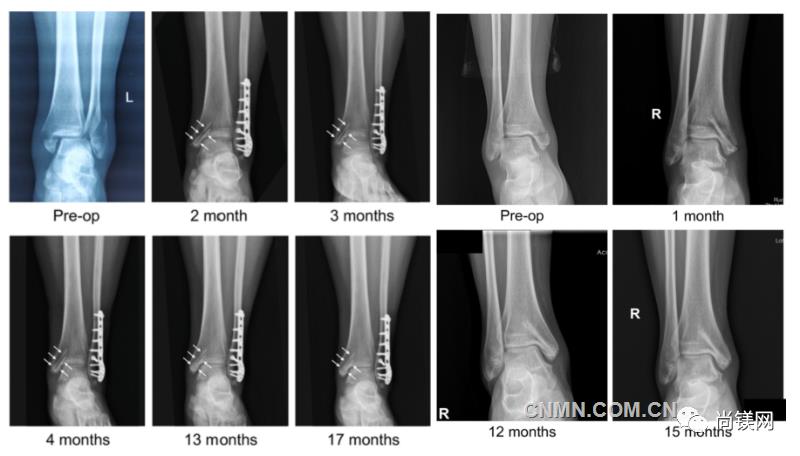

近日,國際骨科臨床轉化期刊《Journal of Orthopaedic Translation》在線發表了由上海交大戴尅戎院士、郝永強教授團隊和丁文江院士、袁廣銀教授團隊合作發表的可降解鎂合金骨釘1-2年的臨床試驗觀察結果,所有患者術后內踝骨折愈合,功能恢復。研究證實了可降解鎂合金螺釘治療內踝骨折的臨床療效及其生物安全性,為全降解鎂合金植入物等高端醫療器械進一步的臨床推廣應用奠定了堅實基礎,相關成果以“Effectiveness and safety of biodegradable Mg-Nd-Zn-Zr alloy screws for the treatment of medial malleolar fractures”為題在線發表于Journal of Orthopaedic Translation,27 (2021) 96–100。這是國內首個可降解醫用鎂合金臨床試驗的公開報道,也是國際首款含有功能涂層的可降解鎂合金骨釘的臨床試驗結果的公開報道,具有里程碑意義。